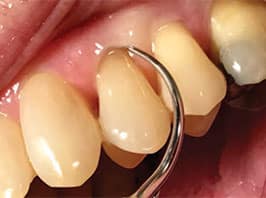

diameter and long ultrasonic insert/tip for

larger burnished/residual calculus.Figure provided by WILL CLEARY

The lack of bleeding on probing is positive in assessing health.8,10,11 If bleeding on probing is identified, inflammation is present; therefore, it is wise to instrument these areas with extra diligence.12 A careful examination of the bleeding on probing site(s) is indicated to determine if residual calculus or newly formed deposits are present. For either type, a site-specific UIT is needed. For example, bleeding in a deep and narrow 7 mm pocket signals that a very long UIT is indicated to reach the base of the pocket and its corresponding walls. If the calculus is burnished or residual, a wider diameter and long UIT is needed (Figure 2). A “top down” approach with a higher power setting is indicated due to the tenacious and larger deposit (Figure 2), followed by a thinner UIT. However, if light deposit is detected, a very thin diameter and long UIT suffices with the technique described above (Figure 3).